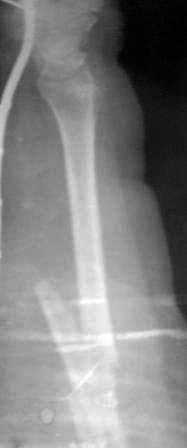

Пациентка 49 лет, по поводу перелома обеих костей предплечья оперирована в марте месяце « и/м остеосинтез спицами», через 4 месяца спицы удалены , антибиотикотерапия и фиксация гипсовой повязкой продолжена, но, учитывая что образуются ложный сустав, госпитализирована.

Повторно открывать зону перелома никак не хочется, учитывая р-картину! А что если закрыто рассверливать к/м канал ( как при БИОС), и КДО аппаратом Илизарова? Уважаемые коллеги помогите советом! Извиняюсь за плохое качество р-снимков!